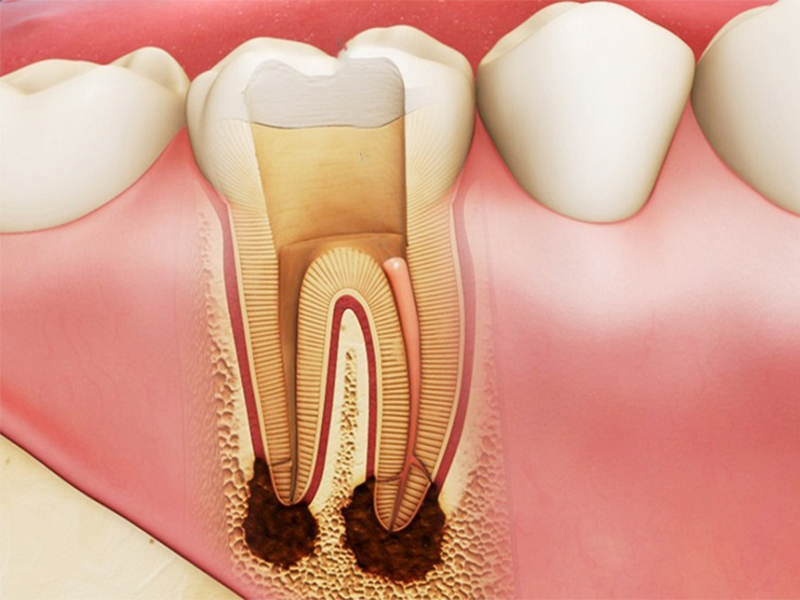

Răng khôn mọc lệch nếu không được điều trị kịp thời sẽ gây ra nhiều biến chứng nguy hiểm như:

Phần va chạm với răng kế cận sẽ khiến đau nhức toàn bộ vùng răng khôn phía trong, có thể khiến răng bên cạnh bị sâu răng, viêm tủy răng,…

Dẫn đến sự hình thành các u nang răng, thậm chí có thể gây hỏng răng số 7 nếu không nhổ răng khôn nằm ngang kịp thời.

Có thể gây xô lệch cả hàm răng nếu để tình trạng răng khô mọc lệch kéo dài quá lâu

Bị đau nhức âm ỉ kéo dài do răng khôn mọc lệch, sưng nướu, kèm áp xe, đau đầu, nóng sốt,…

Răng khôn (hay răng số 8) là chiếc răng mọc cuối cùng trên cung hàm, khi tất cả các răng khác đã mọc đầy đủ, xương hàm đã phát triển vững chắc và nướu cũng trở nên dày hơn. Do đó đôi khi việc này khiến răng khôn mọc khó khăn hơn sẽ gây ra tình trạng răng khôn mọc lệch.

Dưới đây là các kiểu răng khôn mọc lệch gây khó chịu, đau nhức cho người bệnh và cần được xử lý kịp thời để tránh các biến chứng nguy hiểm.